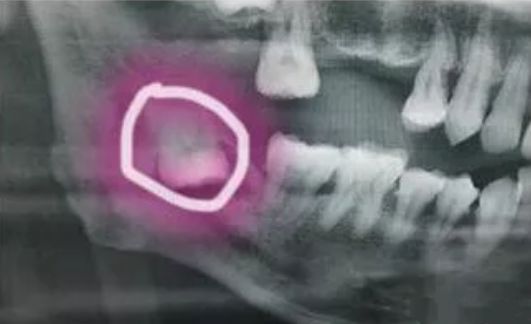

身心俱疲的杨先生来到口腔医院检查,检查结果令杨先生愕然,X牙片显示,杨先生的智齿掉到了左侧下颌骨内侧的深部间隙里。医生告诉他,如果不尽早取出智齿,会导致面部间隙感染并引起严重的后果。由于该院医疗技术有限,便为杨先生联系上武汉大学口腔医院请求帮助。

医师表示,由于患者的智齿位置深,朝舌向倒置生长,紧贴下牙槽神经管,而且舌侧骨壁薄弱,当地医生拔牙时可能没注意,并且这颗智齿的位置一直伴随着颌骨的运动而改变。